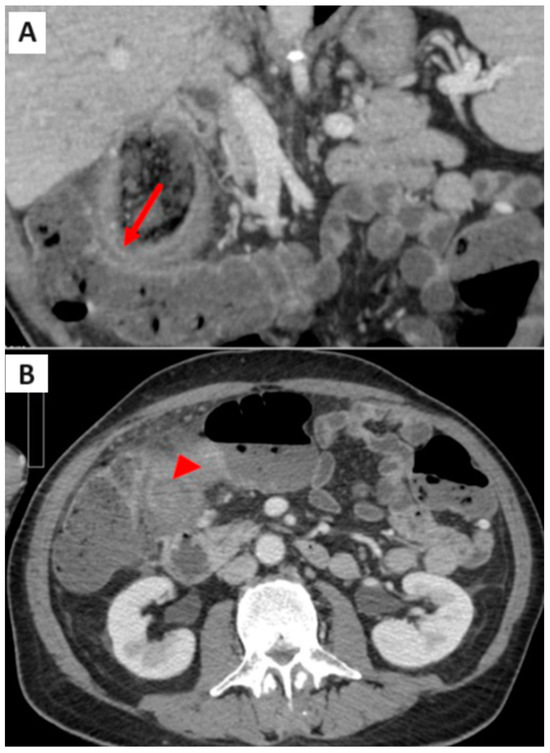

2. Case Report